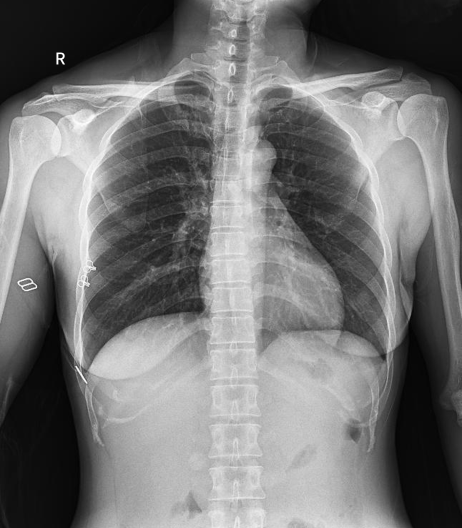

普利德醫(yī)療自主研發(fā)的新一代數(shù)字化X線透視攝影系統(tǒng),可應用于DR攝影、數(shù)字透視、數(shù)字造影以及可視化精準DR拍片等多種臨床X線檢查領域。

● 17*17英寸的超高清像素動態(tài)平板探測器,更大的視野范圍,無需移動即可觀察整個動態(tài)過程,避免拖尾、噪聲對圖像的影響;

● 高效動態(tài)平板技術,圖像不會有幾何畸變,提供高分辨率和精確的圖像,為醫(yī)生臨床診斷提供精準依據(jù);